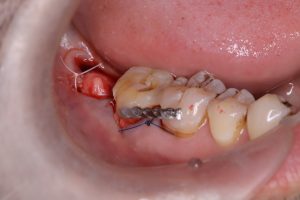

破折している歯を抜歯し、親知らずが収まるように骨の形態を少し調整した後、抜歯した親知らずを移植しました。

下の写真は移植後です。抜歯した部位には、抜歯創面の保護材であるコラーゲンスポンジを充填しています。